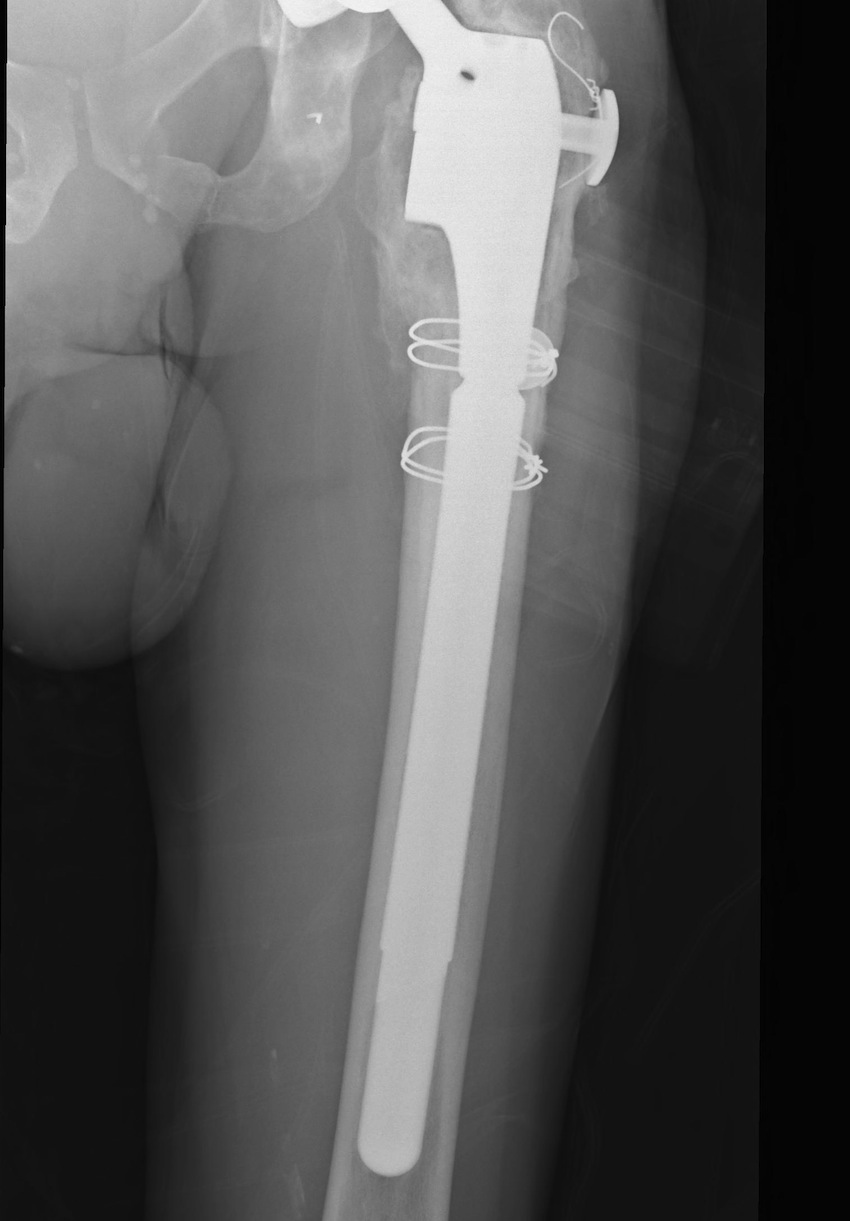

D. Bulk Structural Proximal Femoral Allograft

Indications

- proximal defect > 3 cm

Technique

- desired stem cemented into allograft

- press fit distally into host femur

- step cut graft host junction

- secure cerclage wire and onlay cortical strut

- proximal host bone wrapped around allograft with ABD preservation

- very important – abductor mechanism must be secured and protected